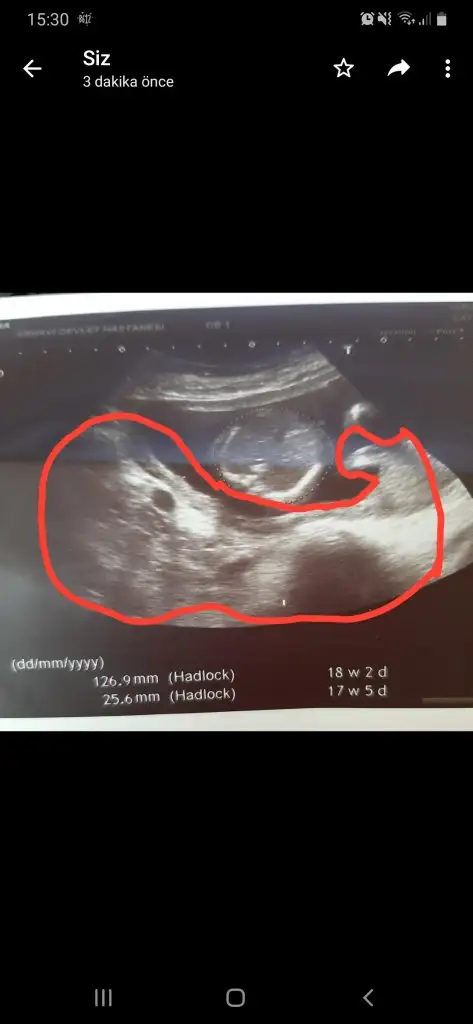

Bacaklarin durusu cok sevimliBiz doktordan çıktık. Cinsiyetimiz hala belli değil

Ama ağız ucuyla kız diyelim dedi.

Şu fotoğraftaki klitoris mi yoksa pipi mi siz bakın bakalım teyzeleri

cinsiyetimize daha tam net birşey söylemedi pozisyonu yakaladığında bacak arası bana boş geldi galiba kız emin olmak için 15 gün sonra bakalım tekrar dedi bizde de durumlar böyle